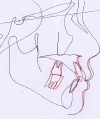

カテゴリー:Class Ⅱ division 1(抜歯症例)

大臼歯関係がclassⅡ、overjet 6mm以上、U1-SN 110度以上、ANB 6度以上が望ましいという条件は第二症例と同じ。FMAの条件がはずれた代わりに、抜歯ケースとして治療することを必須とする。

第2症例に比べると多少条件が緩和された平均的な出っ歯のケース。通常は抜歯して治すことが多いので、付帯条件としても難しさはない。矯正歯科医が日常的に良く遭遇しているケースといえる。第1症例と出題の意図としては同じで、おそらく日常的なケースとして、仕上がりの緻密性を評価する課題と考えられる。